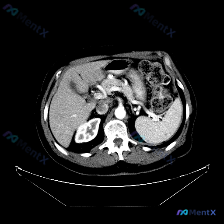

整理了一份有点「反转」的影像读片资料,感觉挺考验临床思维的,分享出来一起理理思路。 --- 一、影像基本信息 这是一张腹部CT横断面软组织窗图像,预设的观察焦点是「脾脏病变」。 二、结构化读片所见(客观描述) 按照读片常规扫了一遍全腹: 1. 肝脏、胆囊、胰腺:形态、大小、密度都正常,轮廓光滑,胰周...

最近看到一个有意思的影像病例,预设是要讨论「脾脏病变」,但看完影像报告和分析后,发现核心其实是「澄清矛盾」,整理一下思路和大家分享。 --- 先看完整的影像观察结果 这是一份腹部CT横断面的分析: - 实质脏器:肝、胰、脾、肾都大致正常——肝脏密度均匀,胰周脂肪间隙清晰,脾脏形态/大小正常、密度均匀...